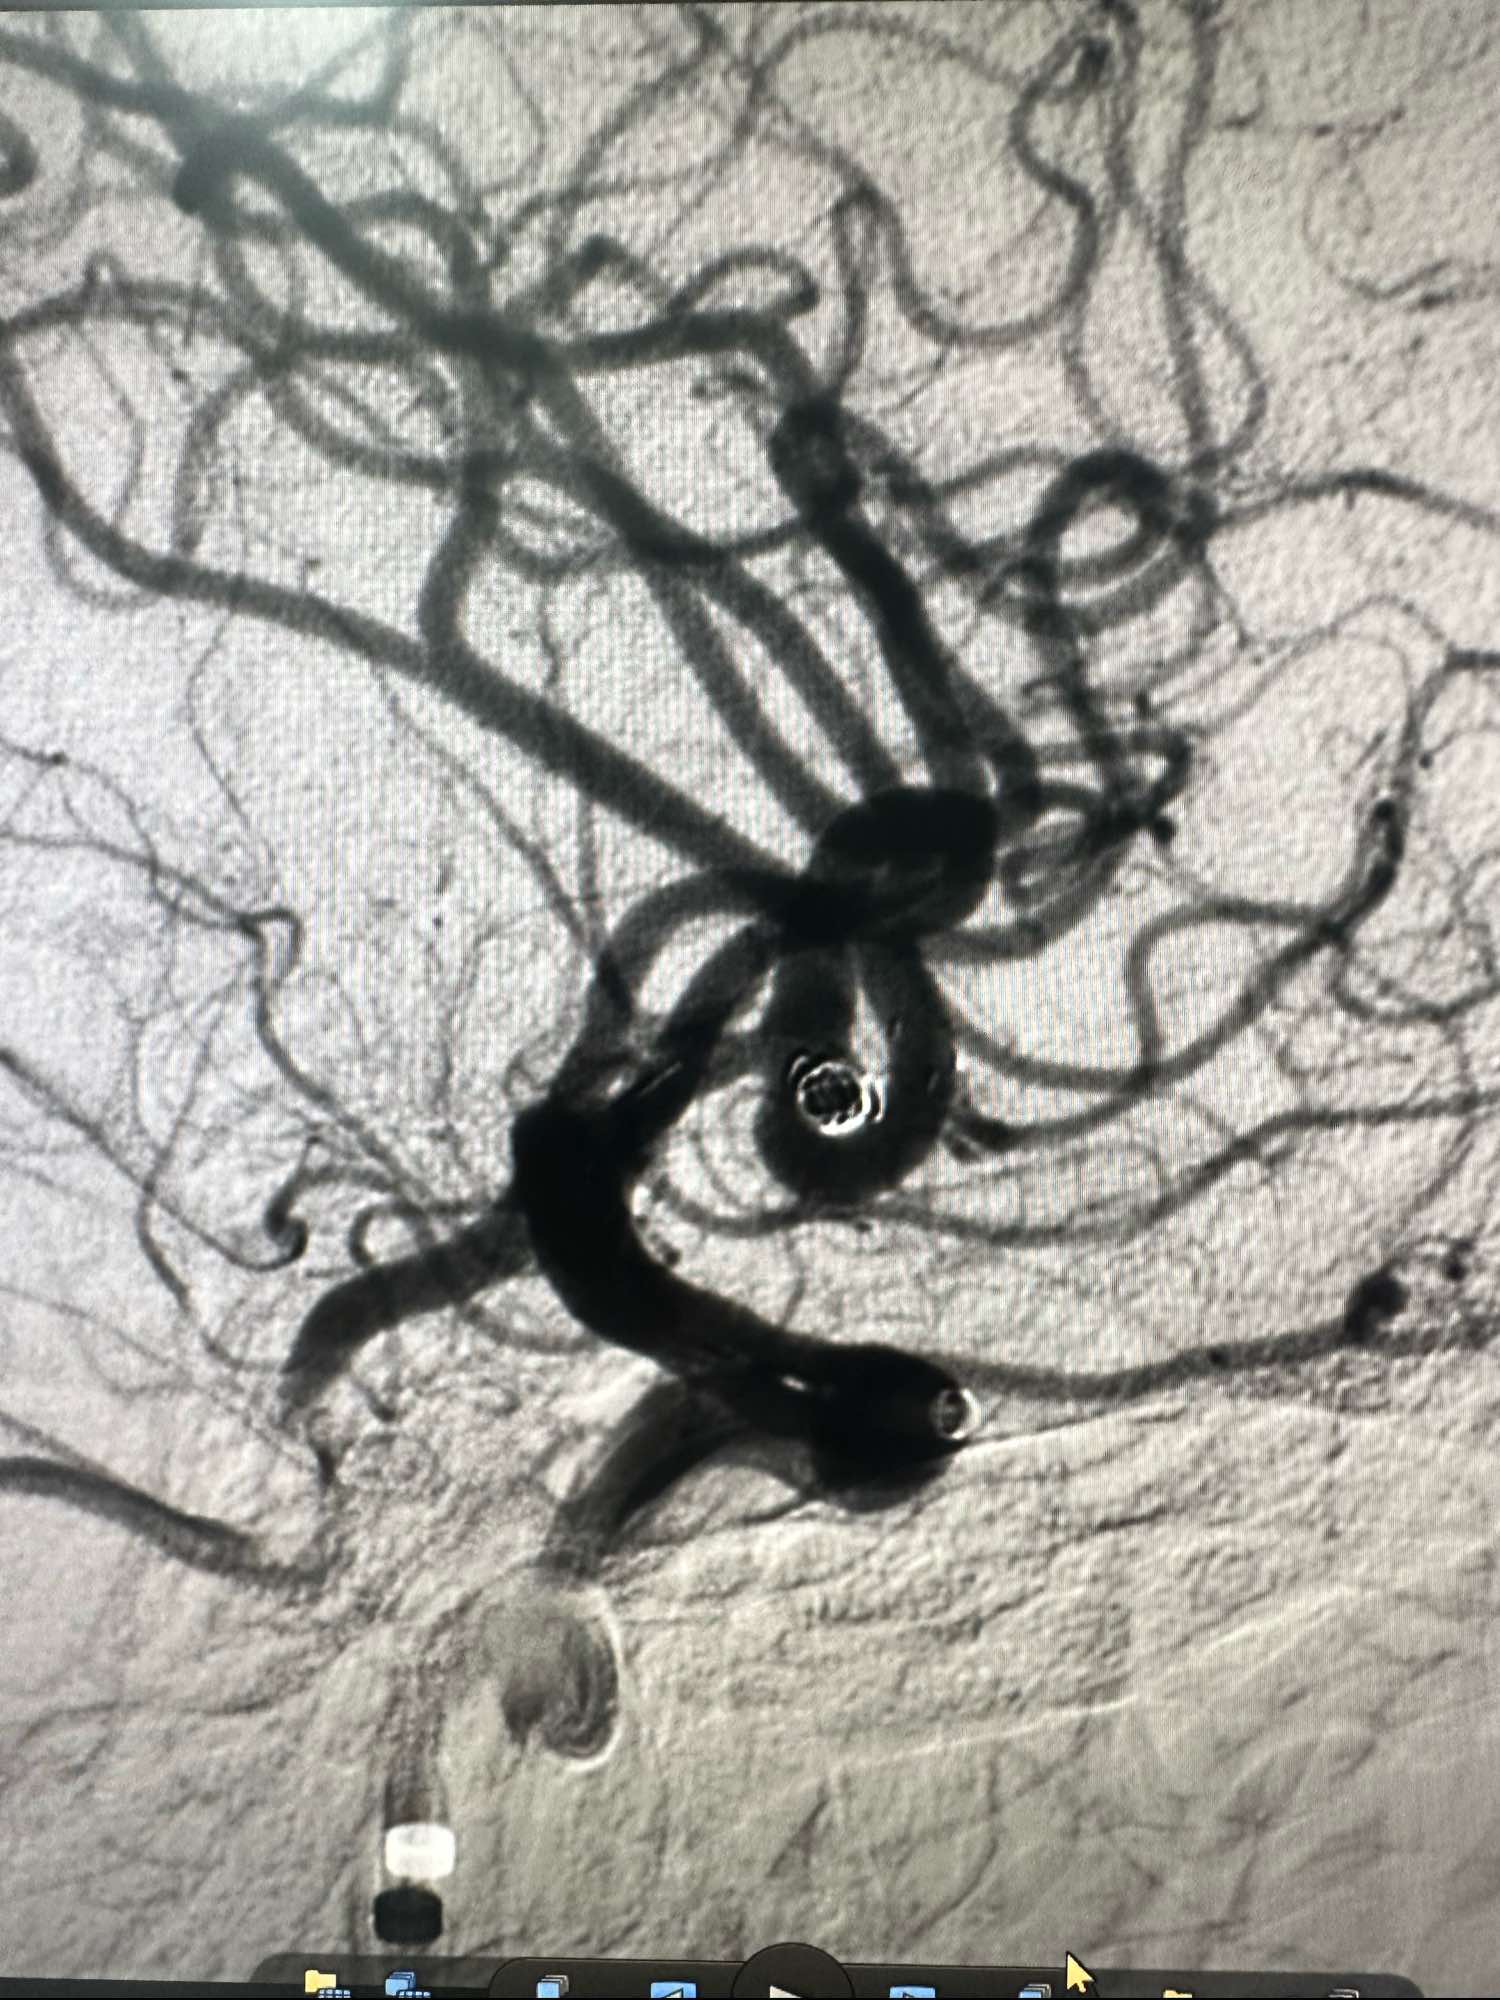

通路为COOK长鞘加上6F的115的银蛇中间导管,刚开始的时候就发现C1痉挛严重.术中给予尼莫通动脉内滴注,痉挛缓解

支架导管选择SL-10,超选下干,角度有点刁钻,采用将支架导管塑形成猪尾巴形态,瘤内成攀后进下干.

Enchon-10弹簧圈导管塑形后直接进入动脉瘤内

第一枚圈选择3*8的加奇的3D,出了几个襻后直接释放Atlas支架3*21